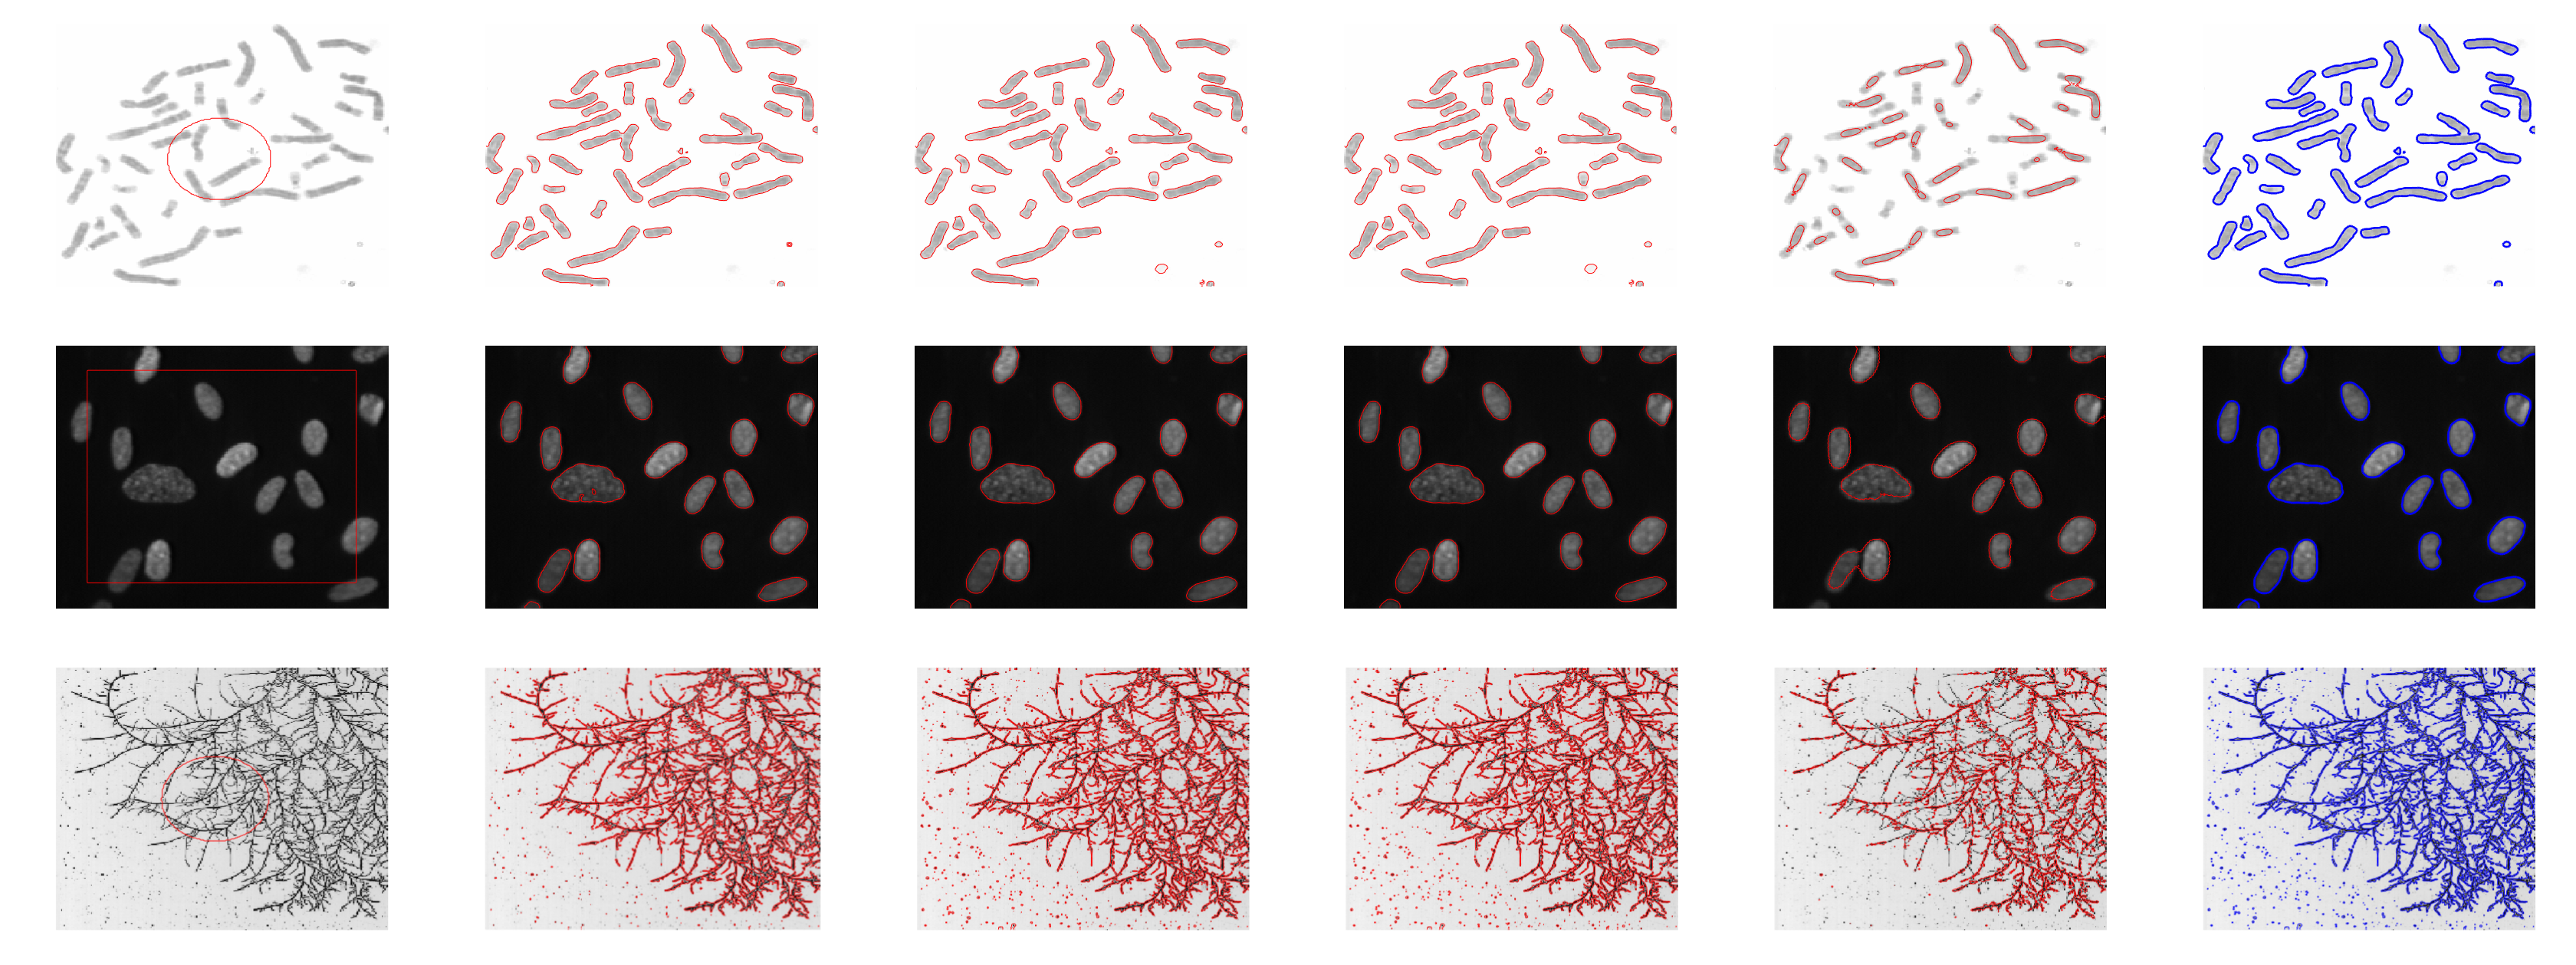

To further verify the efficiency of our model in terms of image segmentation, we conducted experiments on a bio-medical grayscale image dataset [46]. As shown in the first row of Fig. (11), we attempted to extract the chromosome, whereas in second row, we tried to find algae from a dark background. Finally, the last row shows the segmentation of a fungus. These bio-medical grayscale images have different variations in intensity, which make it difficult to segment. From Fig. (11), we can see that the proposed model conveniently extracts all the required objects from these bio-medical images.

IV-D color images

We further tested our model by segmenting color images. Figs. (12) and (13) show the segmentation of the color image datasets. In Fig. (12), the first three images are chosen from the MSRA 1000 dataset [44][47]. The first column shows the original image with the initial contour, whereas the remaining columns are the results of the CV, LBF ,LIF, SDREL, and proposed models. The experimental results show that the CV, LBF, and LIF models are unable to segment the object from the color images, whereas SDREL shows prominent results. However, the segmentation results of our model on the MSRA dataset are more accurate and reliable. Similarly, the last row of Fig.(12) shows a fatty liver image in which the purpose of the segmentation is to extract the fatty circle from the image. All the applied models extract some parts of the fats from the liver, whereas our model achieves the best segmentation and extracts all fat circles from the liver image. However we still have gap to improve the segmentation accuracy of the region based ACMs such color images.